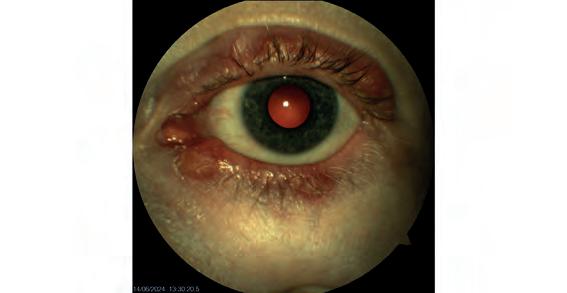

A retinal detachment diagnosed by Queensland optometrist Peter Choc on his Optos Daytona.

A secondary retinal detachment.

Images: Gladstone Vision.